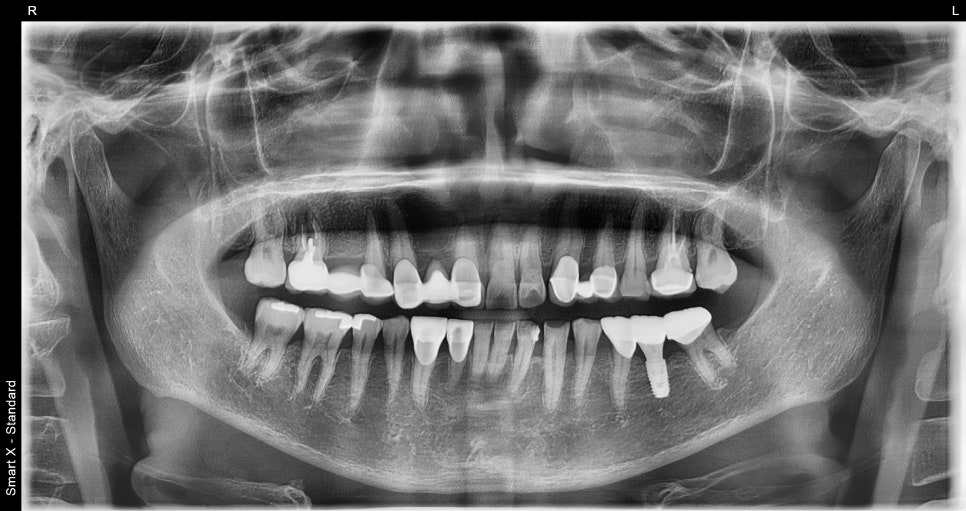

Panoramic X-ray at the first visit

This is the X-ray taken immediately after implant surgery.

During the osseointegration period, we checked the teeth on both sides for any irritation or discomfort, and the patient was advised to live with temporary prosthetics.

Panoramic X-ray immediately after surgery

Final panoramic X-ray